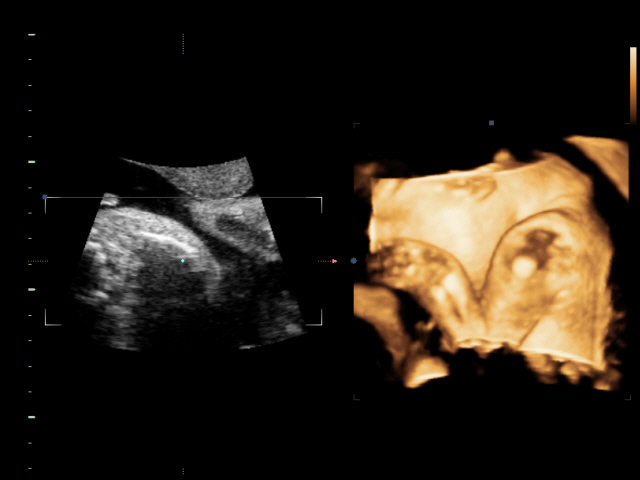

31tt+5 a drobček má 1835g 🙂

bábenko je už v brušku hanblivé🙂)) no ale hlavne že nám dovolilo si ho pomerať🙂))